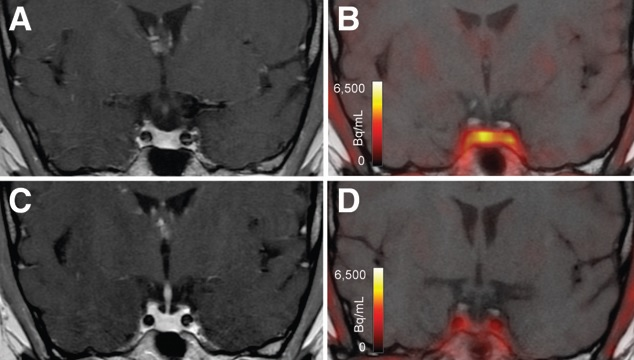

F-18 FDG and Ga-68 FAPI-46 images of a 51-year-old woman with adenocarcinoma with lepidic growth pattern in right upper lobe. (A) Maximum-intensity-projection PET images. The lesion had F-18 FDG uptake below blood pool level but was strongly Ga-68 FAPI-46-positive. CT-guided biopsy led to pathologic diagnosis of adenocarcinoma, and the patient was treated by stereotactic body radiation therapy because of functional inoperability. Image courtesy of the Journal of Nuclear Medicine.